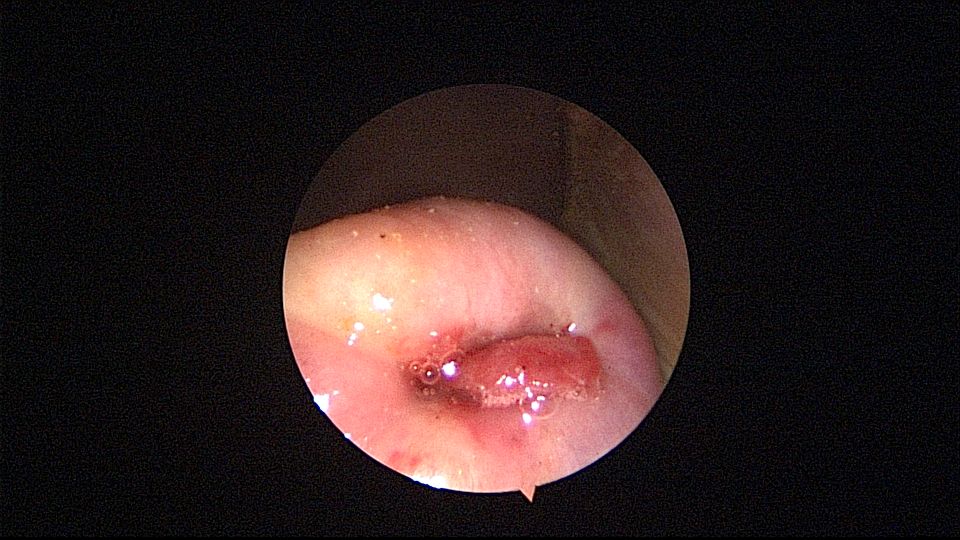

患者55岁,G1P1,顺产1次。安环34年,闭经半年,2天前外院取环失败,感下腹疼痛不适。术前复查B超,子宫前壁肌瘤直径4cm,宫内节育器回声。术中见子宫前倾后屈位,宫颈外口见息肉,镜鞘旋转扩宫进入宫腔,O型环位置正常,宫腔右前壁见直径2.5cm肌瘤结节突向宫腔,取环钩顺利取出节育环,宫腔无其他异常。该患者常规取环时未膨宫,子宫位置特殊,加之子宫受刺激后肌瘤凸向宫腔,可能对取环器械形成支点及杠杆效应,取环器械难以到达节育环位置,导致取环失败。